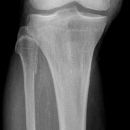

distaler Unterschenkelschaft

Spiralfraktur Tibia